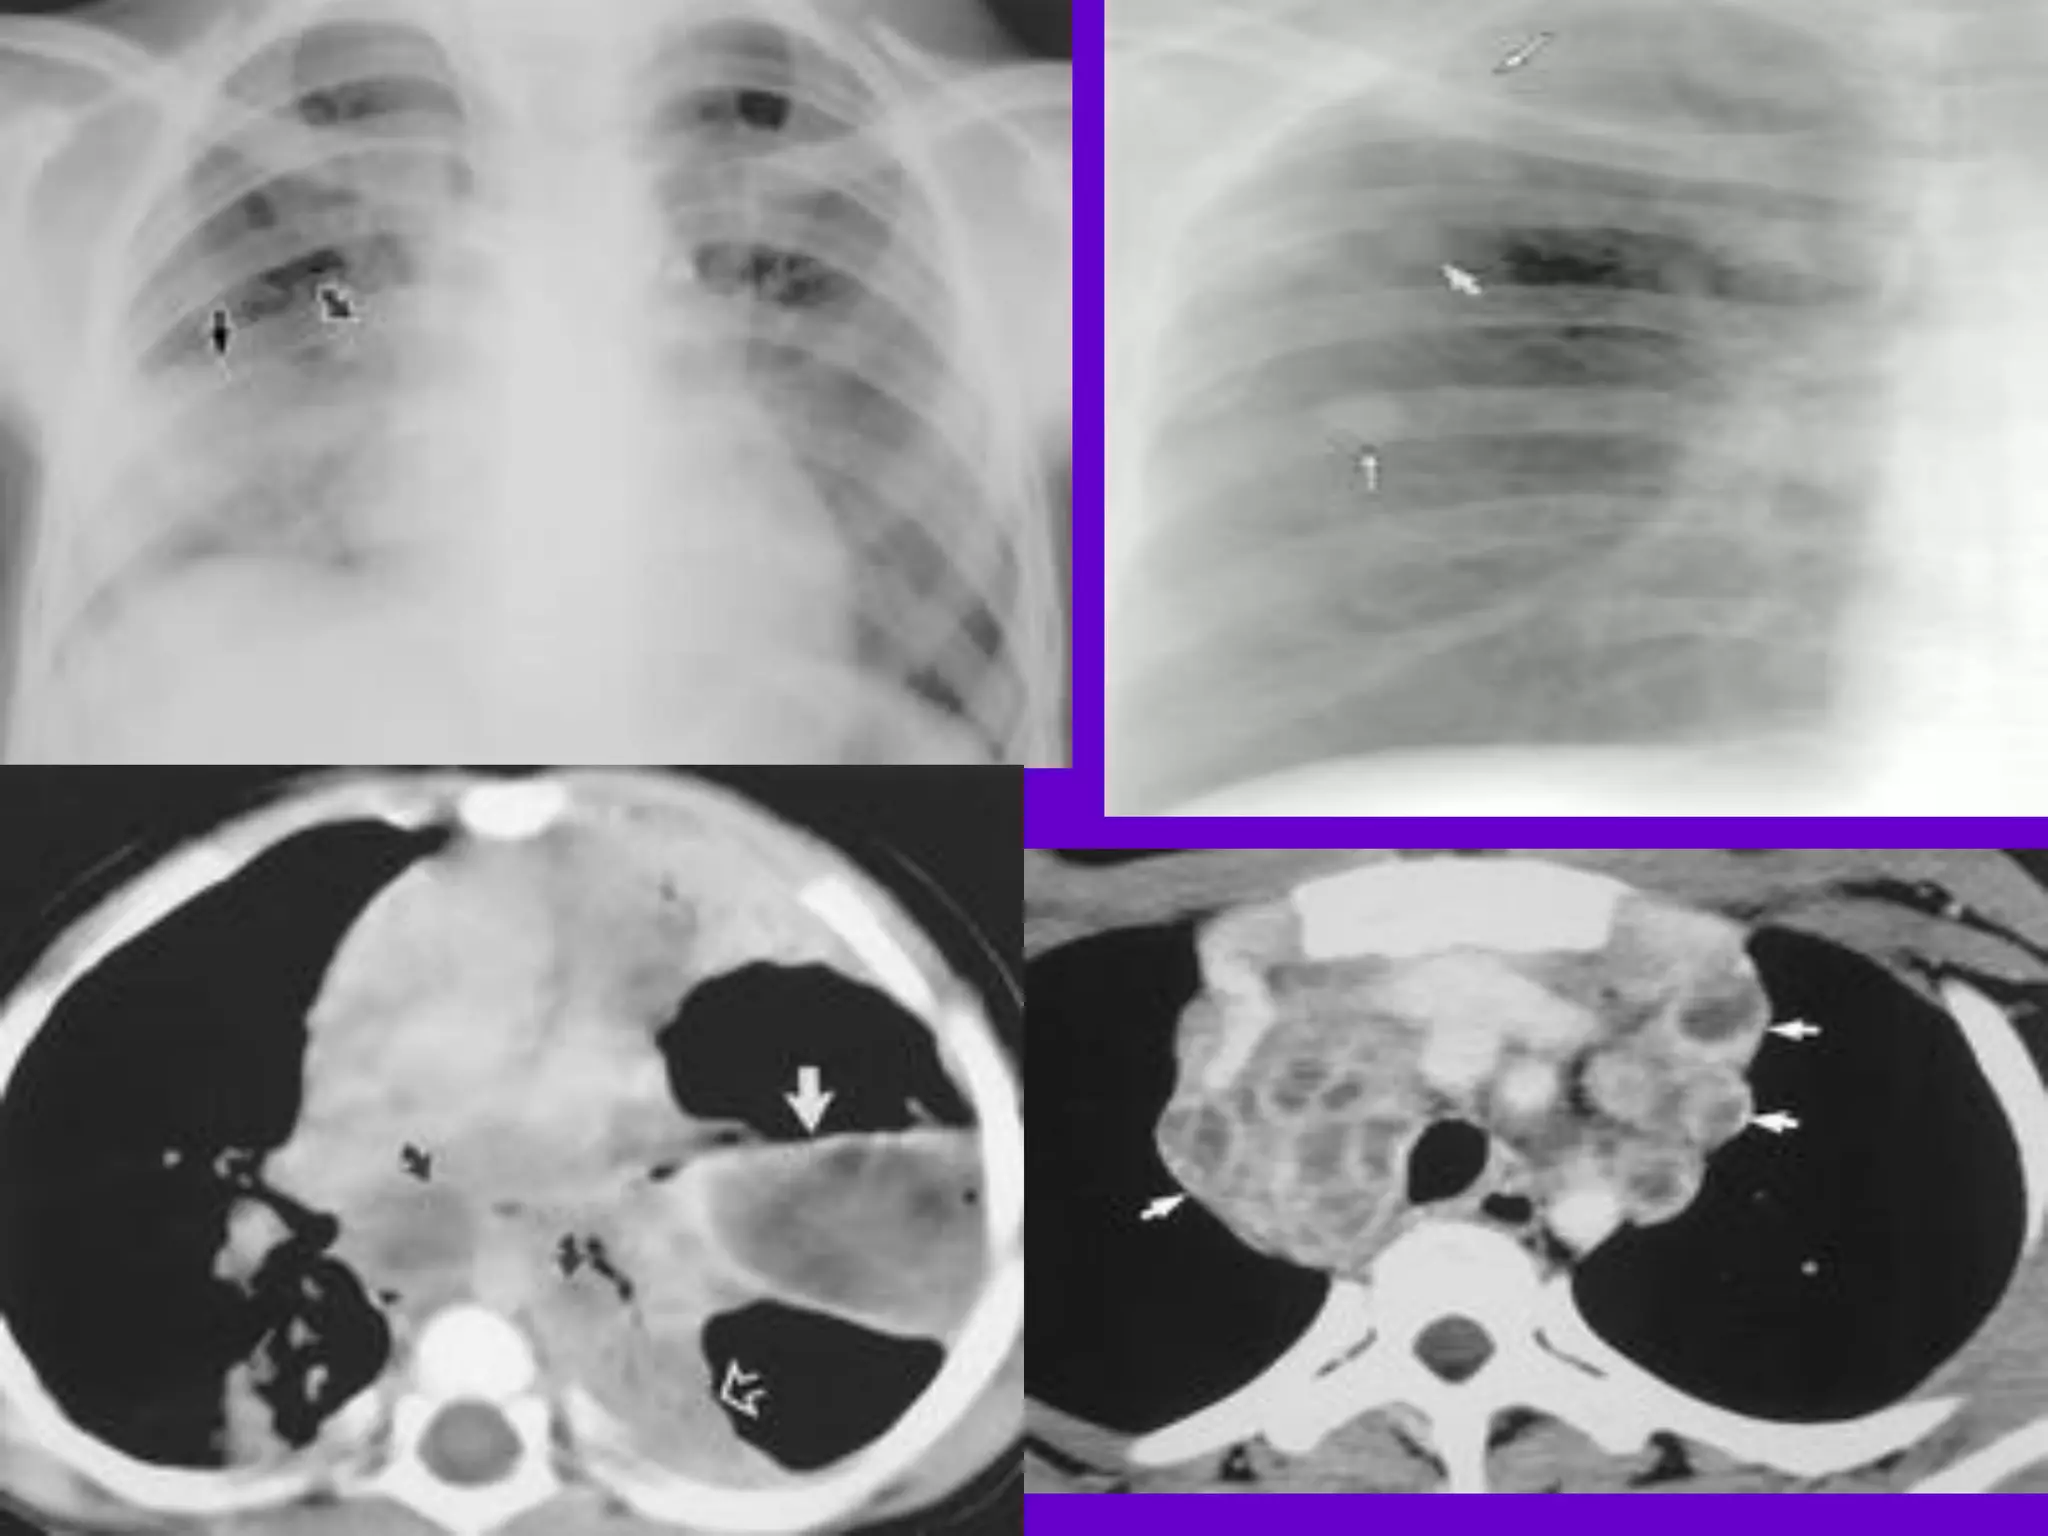

CT Scan andMRI Scan in the diagnosis of TB 􀂄 The advent of CT and MRI imaging in the last two decades has redefined the approach in analysis of various diseases including TB.* 􀂄 CT and MRI have shown several advantages over conventional radiology in early diagnosis and follow-up of TB in different parts of the body. *Buxi TBS Indian J Pediatr 2002;69:965-972

• 94.

Pulmonary TB : LobarPneumonia 􀂄 CT is superior than plain CXR in picking up the consolidation, atelectasis and the hilar LN thereby making the diagnosis easy. 􀂄 MRI reveals some of these changes, however, CT is the diagnostic modality of choice in such cases. 􀂄 Bronchopneumonia 􀂄 On CT it is usually B/L and widespread, not always symmetrical involvement of lungs. 􀂄

• 95.

Hilar and Mediastinal Lymphadenopathy CTand MRI depict the hilar and mediastinal LN equally well. 􀂄 Calcification in the nodes is however better seen on CT. 􀂄 Necrosis is seen as focal areas of low attenuation on a CECT. 􀂄 On MRI focal necrosis is seen as areas of increased signal intensity on T2W images. 􀂄 EBTB 􀂄 HRCT is sensitive in the detection of early endobronchial spread of disease. 􀂄

• 97.

Miliary TB 􀂄 Earliestform of miliary TB is detectable on HRCT. 􀂄 Coalescing nodules result into patchy irregular opacities and HRCT shows this variation effectively and has been described as “snowstorm appearance”. 􀂄 HRCT shows cavitation, which is not evident on plain CXR. Pleural Effusion 􀂄 􀂄 CT is sensitive to diagnose and define even minimal pleural effusion/pleural calcification. 􀂄 Pleural fluid is seen on inversion recovery MR images as areas of increased signal intensity along the inner aspects of the chest wall.